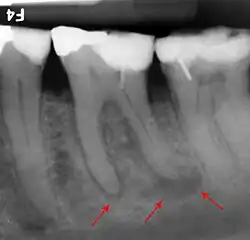

The periodontal ligament becomes inflamed and there may be pain when biting or tapping on the tooth. On an X-ray, bone resorption appears as a radiolucent area around the end of the root, although this does not manifest immediately.[10]: 228 Acute apical periodontitis is characterized by well-localized, spontaneous, persistent, moderate to severe pain.[6]: 125–135 The alveolar process may be tender to palpation over the roots. The tooth may be raised in the socket and feel more prominent than the adjacent teeth.[6]: 125–135

- Radiographs utilized to find dental caries and bone loss laterally or at the apex.